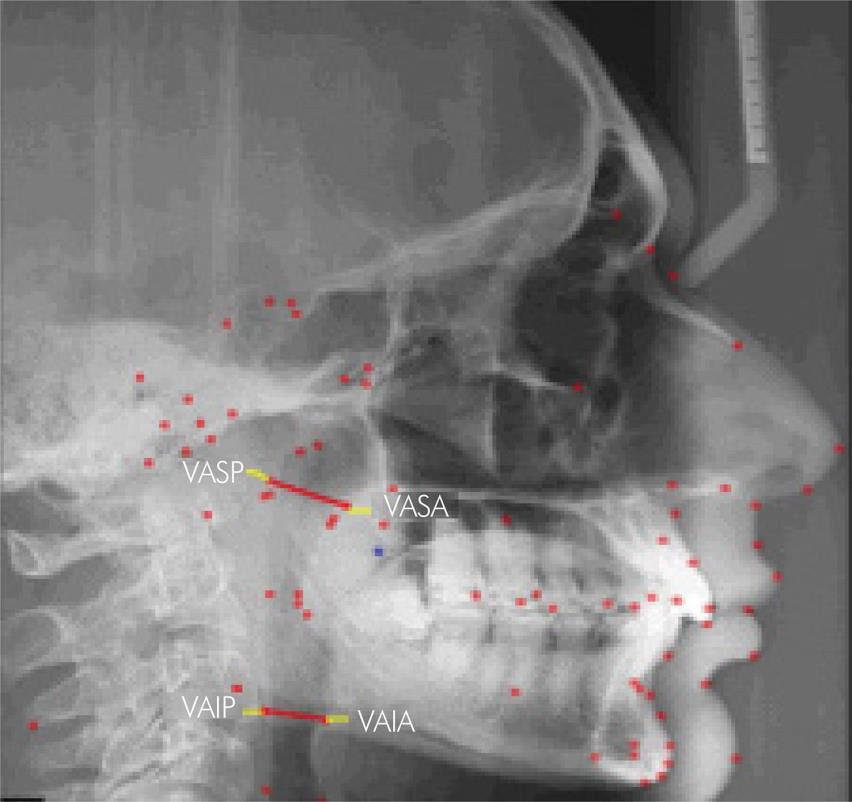

MRI Sagittal View: Patterns of Motion

33%-Movement en bloc, lower AHI

27%-Anterior movement at base of tongue

40%-Elongation, limited anterior movement

Brown EC, et al. Sleep. 2013 Mar 1;36(3):397-404.480